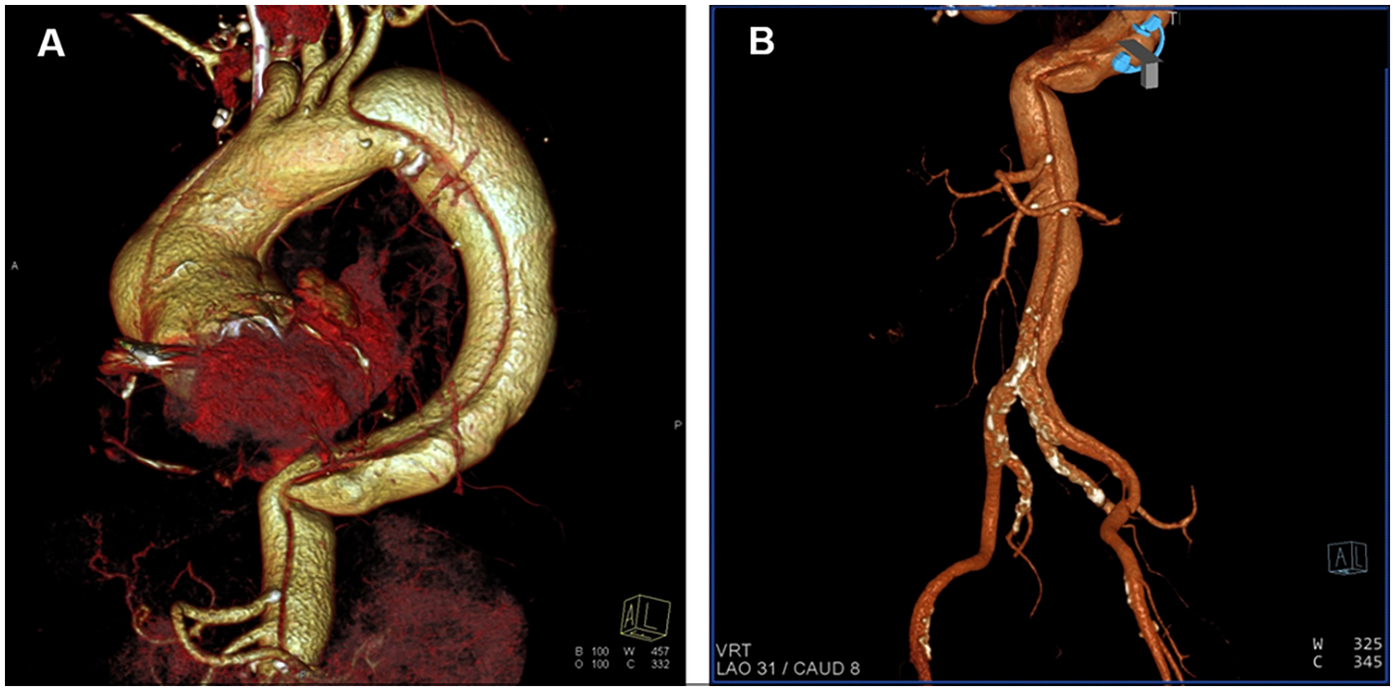

Figure 2

Three-dimensional (3D) reconstruction images from computed tomography angiography. (A) Thoracic reconstruction showing dissection of the ascending aorta, the aortic arch, and the descending aorta. (B) Abdominal reconstruction showing dissection of the abdominal aorta, the left common iliac artery and the femoral artery.

The patient had a long and complex history of illness (Table 1). The patient had been diagnosed with type A aortic dissection for more than 5 years. Computed tomography (CT) revealed extensive dissection involving the aortic root, the ascending aorta, the aortic arch, the descending aorta, the abdominal aorta, the left common iliac artery, and the femoral artery (Figures 1, 2). The diameter of the ascending aorta remained at 83–89 mm after 2019. Because CT angiography failed to detect the site of the intimal tear and because of the lack of technical capabilities, the patient had not received any repair surgery. When the patient started hemodialysis therapy, low-molecular-weight heparin (LMWH) was not administered because of the concerns about inducing dissection rupture. The anticoagulant-free dialysis pattern frequently caused dialyzer clotting, but could still maintain the patient's normal physiological state.